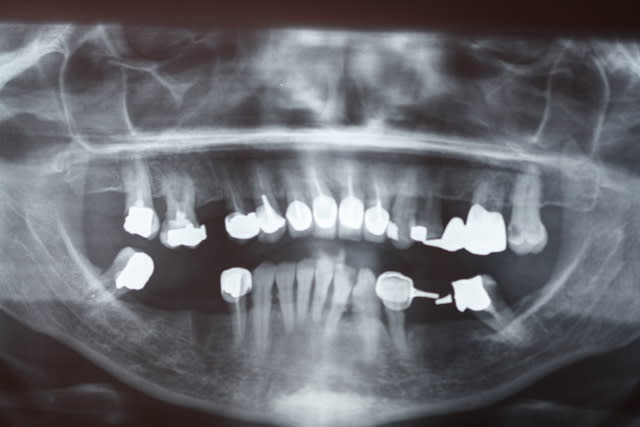

Je vous présente un cas que je viens de finir , il n'était prêt pour l'ADF . C'est un cas complet où j'ai pu exprimer mon art dans tous les domaines , endo , paro , ortho , prothèse .

Bon je réponds donc à l'élongation coronaire de la 32 . Cela m'a semblé nécessaire après le traitement ortho de la 11 , l'équilibration est à la fois diagonalement réussie et très harmonieuse . Il ne s'agit donc pas d'un surttt , d'ailleurs ce n'était pas dans le devis et il n'y eut pas de surcoût pour la patiente .